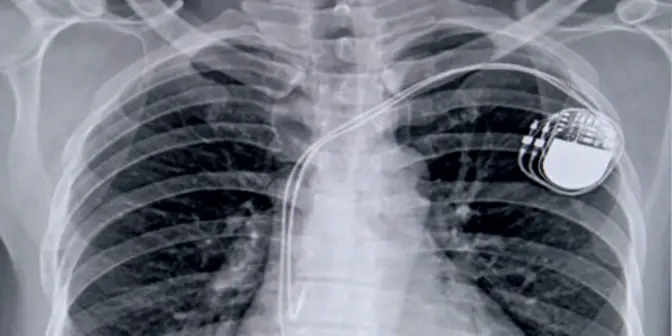

Komponen Utama dalam Alat Pacu Jantung

Agar bisa menjalankan fungsinya dengan baik, pacemaker memiliki beberapa komponen penting:

- Pulse generator

Berisi baterai dan sirkuit elektronik yang menghasilkan sinyal listrik. Bagian ini biasanya ditanam di bawah kulit, di dekat tulang selangka. - Leads (kabel elektroda)

Kabel tipis dan fleksibel yang menghubungkan generator dengan jantung. Leads ini mengirim sinyal listrik sekaligus membawa informasi balik dari jantung ke alat. - Elektroda

Ujung kabel yang menempel pada otot jantung. Elektroda berperan langsung dalam menyalurkan impuls listrik agar jantung berkontraksi.

Dalam perkembangannya, teknologi terbaru menghadirkan leadless pacemaker, yaitu pacemaker tanpa kabel. Alat ini berbentuk kapsul mungil yang dipasang langsung di ruang jantung sehingga lebih sederhana dan minim risiko.